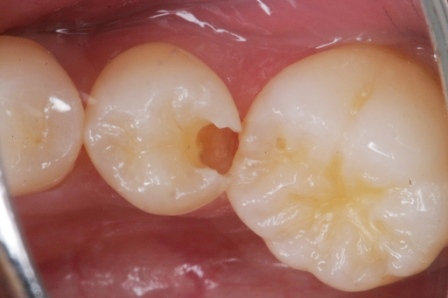

下顎7番の頬側歯茎部カリエスの原因 2025.06.04